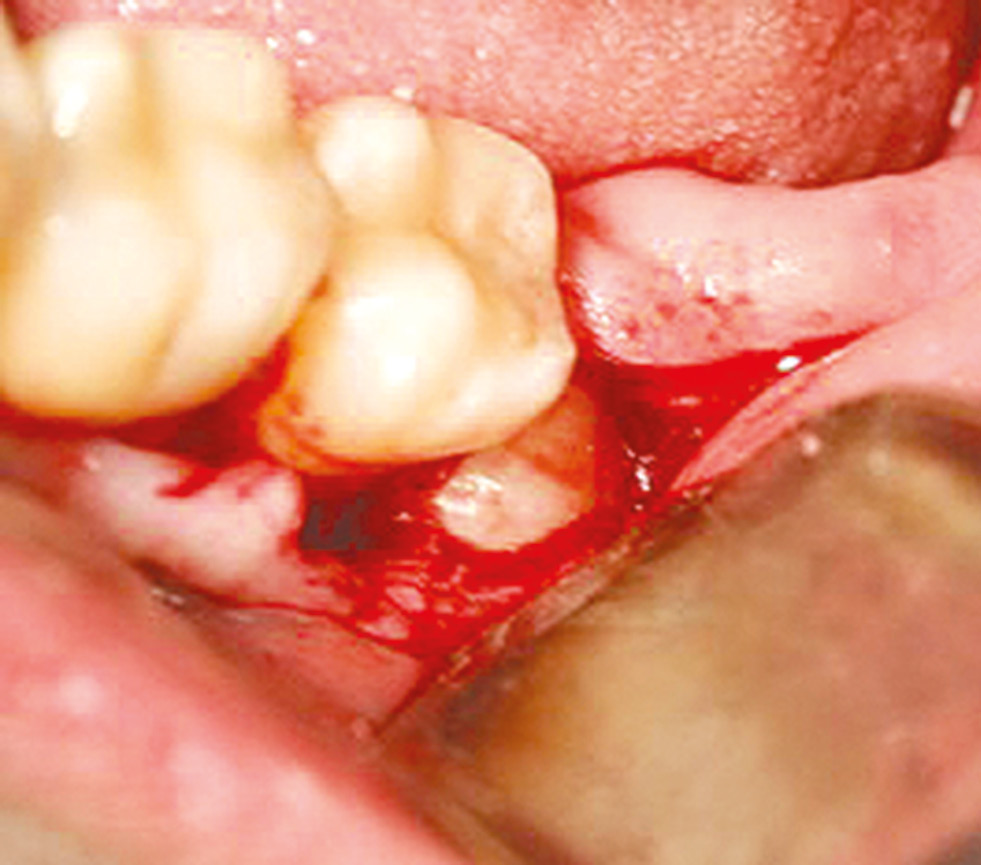

При удалении нижних третьих моляров под проводниковой и инфильтрационной анестезией выполняли разрез в ретромолярной области, в проекции коронки зуба, посередине альвеолярного гребня, и вниз к переходной складке от середины коронки второго моляра (рис. 1).

Рис. 1. Доступ в ретромолярной области.

Fig. 1. Access in the retromolar region.